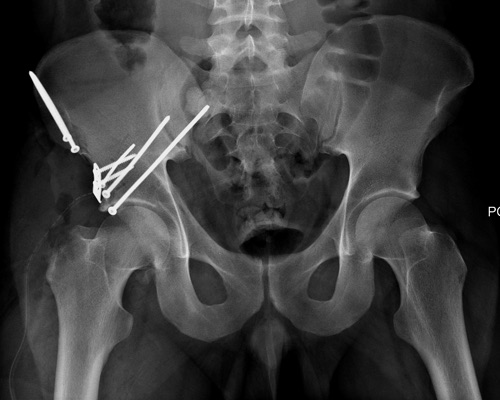

Дискуссия показывает интересные стороны развития тактики лечения переломов вертлужной впадины. Для разработки лечебной тактики сперва надо установить диагноз, и разбор показывает, что не все справляются с такой задачей! Изучение перелома надо начать из стандартных снимков: для переломов костей таза: прямой, inlet и outlet, а для перелома вертлужной впадины - снимки по Judet.

В последнее время, из-за красоты участился показ 3D снимков, хотя надо начать c обычных, и, по необходимости, компьютерная томография с 3D! Без головки бедра 3D покажет общую картину и вовлечение сустава, а более детально только в срезах КТ.

Данная картина показывает очень редкий перелом передней колонны, но перед операцией еще раз надо просмотреть обещанные дополнительные КТ срезы.

По поводу лечения, мнения разделились между открытой репозицией или не открывать! Нельзя подгонять метод под имеющийся инвентарь! Предложенный метод идеальный для damage control при разрыве тазового кольца! Метод Илизарова, как спасательный круг, когда кроме спиц ничего, но времена изменились, везде доступны современные методы фиксации! Наружный фиксатор обязывает вести наблюдение за спицами. И еще, вряд ли аппарат со множественными спицами в тазу даст возможность мобилизовать больного! Кроме этого, установка “трансфрактурных спиц” тоже не простая задача, чем винты, открытым методом!

Представленные слайды Александром из Севастополя, имеет ценность, но, кроме inlet, остальные стандартные Judet рентген снимки должны показать правоту принятого решения. Возможно, здесь фиксация перелома вертлужной впадины, но по рентгену трудно понять!

Вместо огромного аппарата, пластина на крыле и винты через AIIS (anterior inferior iliac spine) из места прикрепления прямой мышцы создали бы более элегантную фиксацию. Насчет отсутствия материала, неужели рядом с “Москоу-сити”, в областном центре, где рекламируются передовые платные услуги, отсутствует элементарные пластины и винты? http://bsmp40.ru/services/pay/travma

Фиксация переломов передней колонны намного легче, чем остальных переломов вертлужной впадины. Любой доступ: Smith Petersen, Stoppa или ilio-inguinal. Как фиксировать перелом зависит от желания врача, можно пустить пластину по pelvic brim (linea terminalis) или более щадящее из верхнего окна пластиной, а переднюю колонну длинными межколонными винтами.

Здесь пример перелома передней стенки, где сохранен принцип фиксации передней колонны. Для доступа Smith Petersen с остеотомией ASIS. Мышца сарториус отодвинута, и сделана ре-фиксация на свое место винтами. При хорошем обзоре, наличие Farabeuf или Jungblud forceps облегчит репозицию.